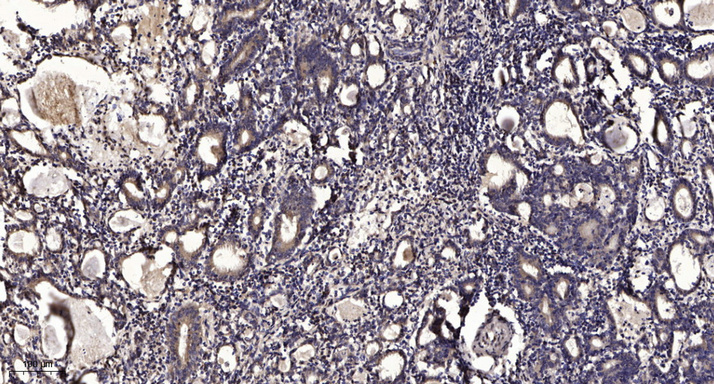

图片:

Formalin-fixed, paraffin-embedded human Gastric adenocarcinoma for SNAT Antibody was diluted at 1:200 dilution in immunohistochemical analysis.